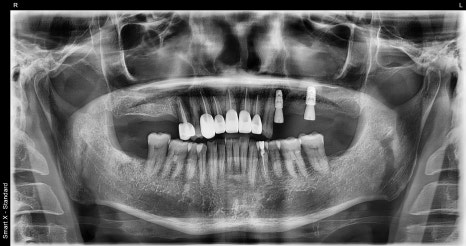

초진 시 촬영한 전체 파노라마 X-ray 사진

정밀 진단 중, 앞니 외상 외에도 오른쪽 어금니 쪽에 진행된 충치와 골 손실이 확인되었습니다.

결국 해당 부위는 발치가 필요했고, 뼈이식과 함께 임플란트 수술이 시작되었습니다.

임플란트 수술 직후 X-ray 및 수술 후 구강 내 모습

치료 전후 파노라마 X-ray 비교 사진 (왼쪽: 초진 / 오른쪽: 치료 후)